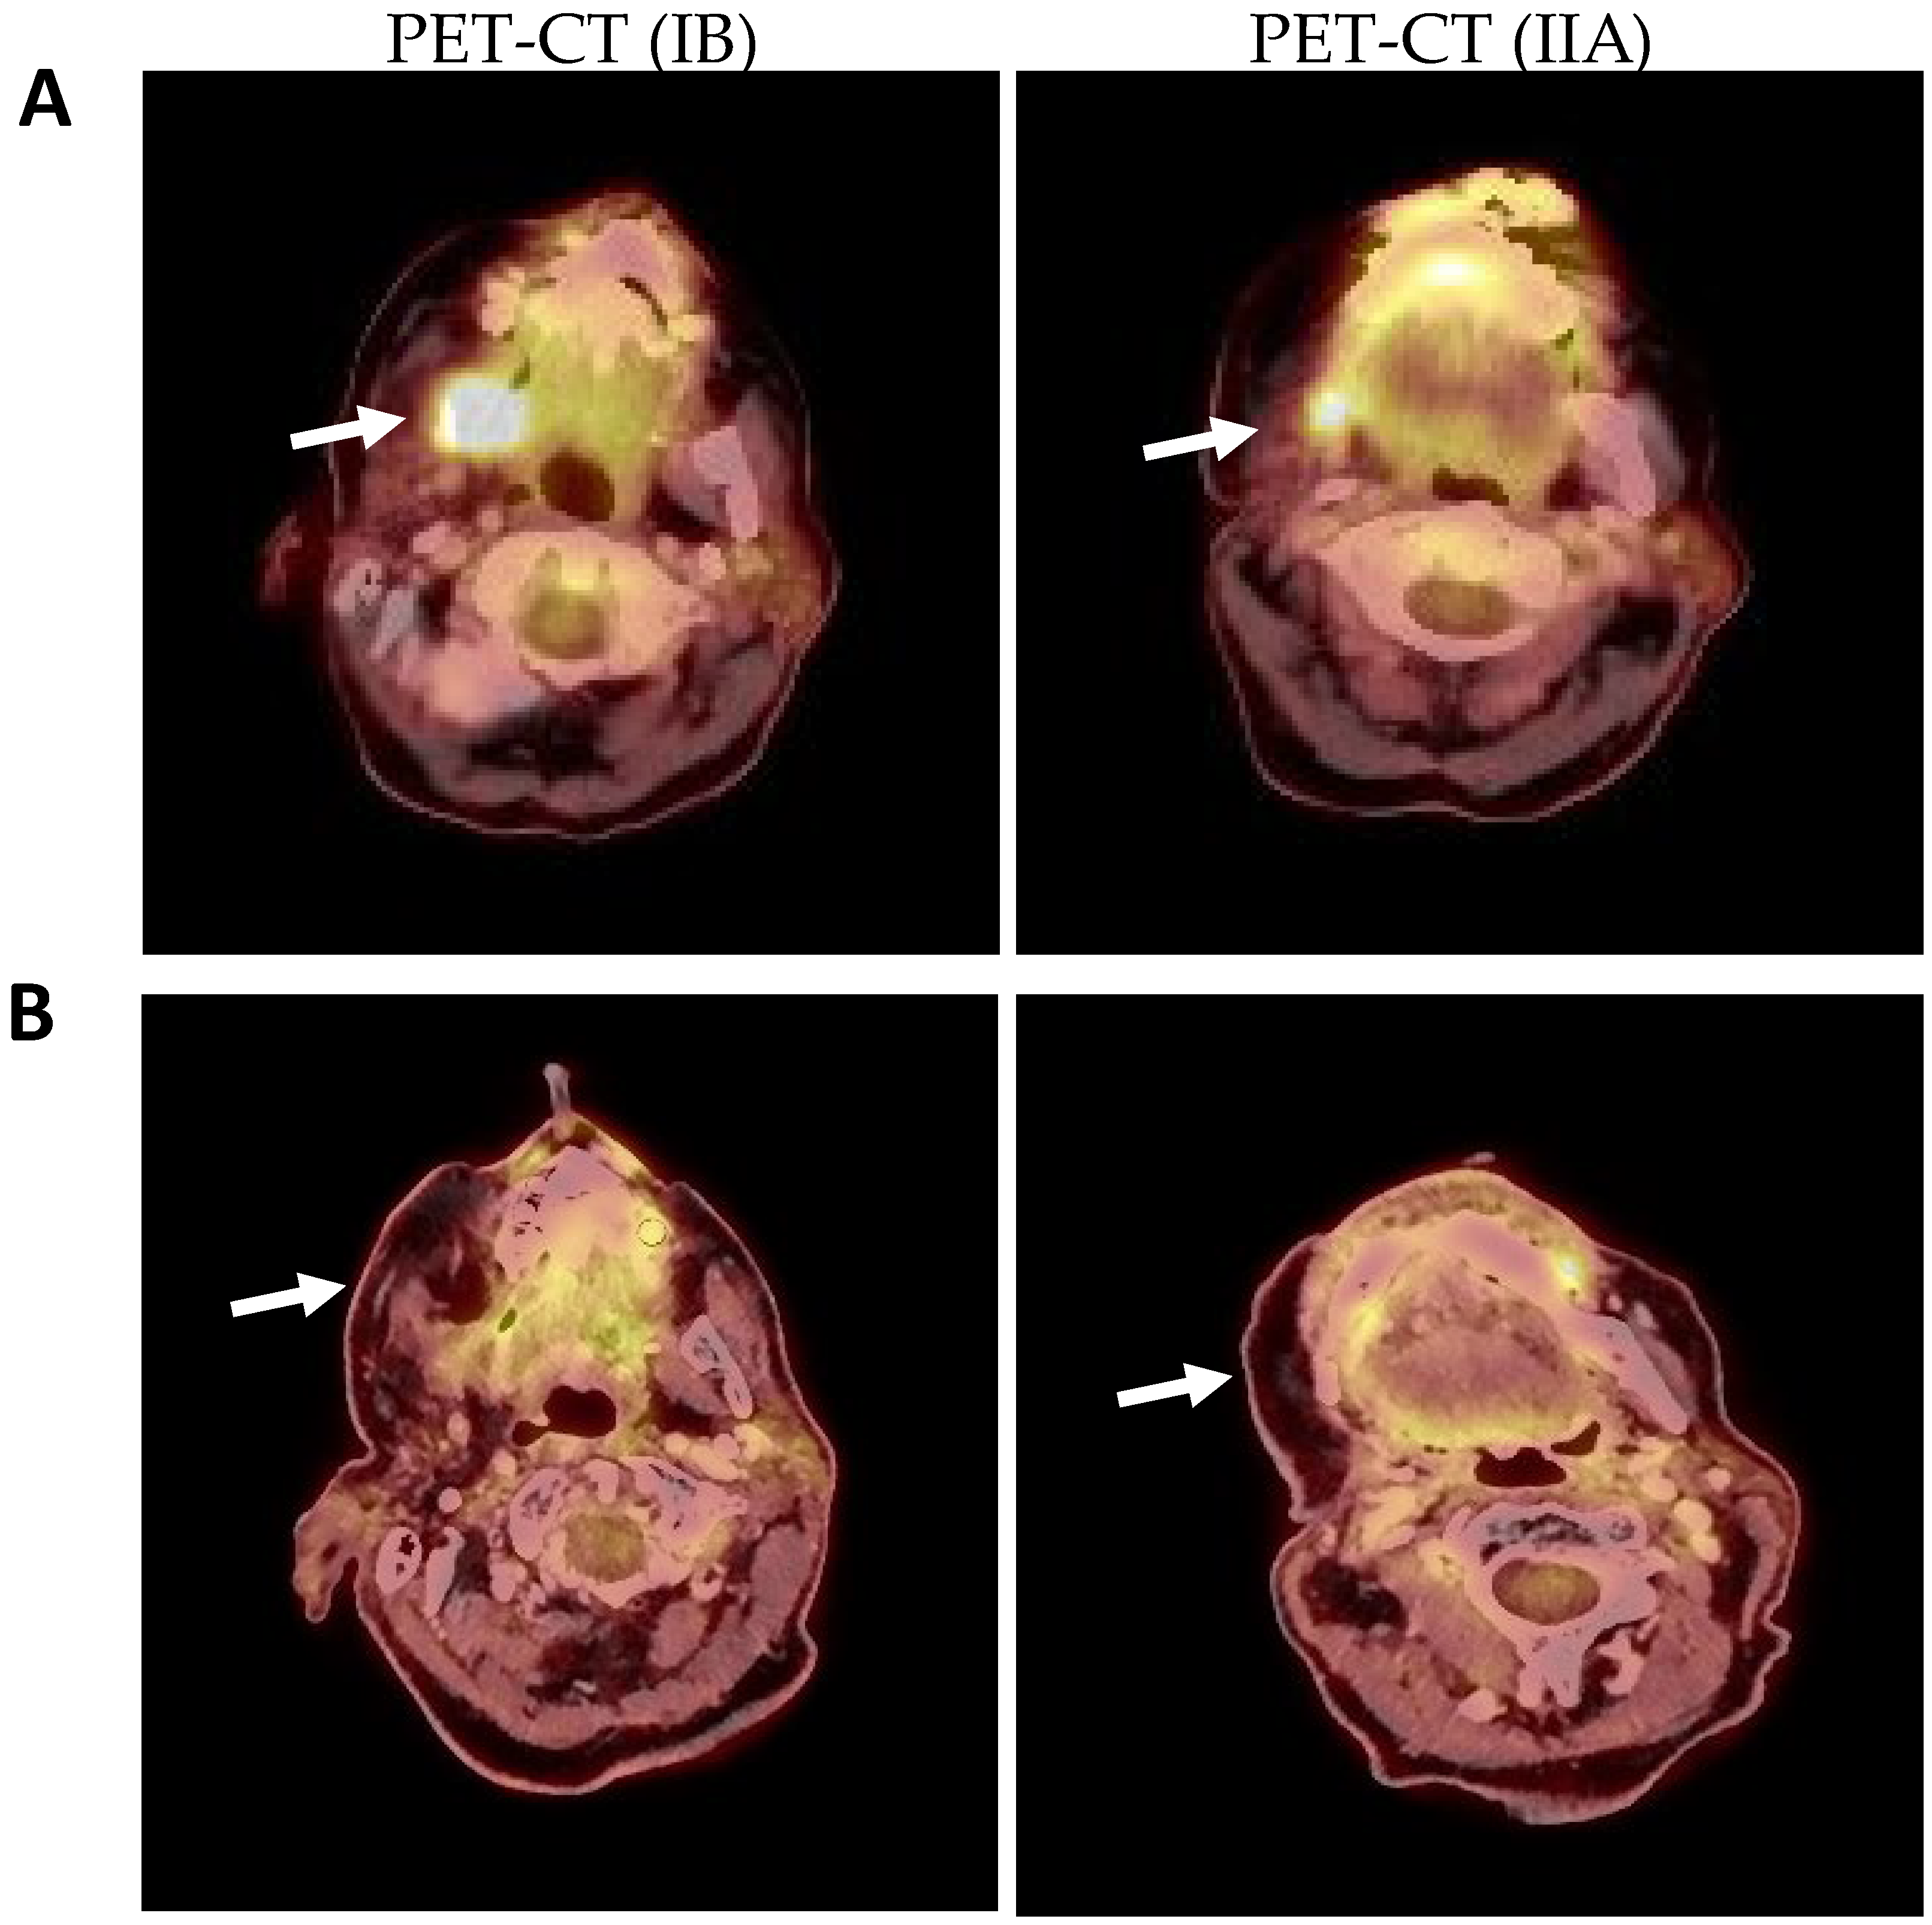

2.1. Clinical and Histological Manifestations of the Tumors